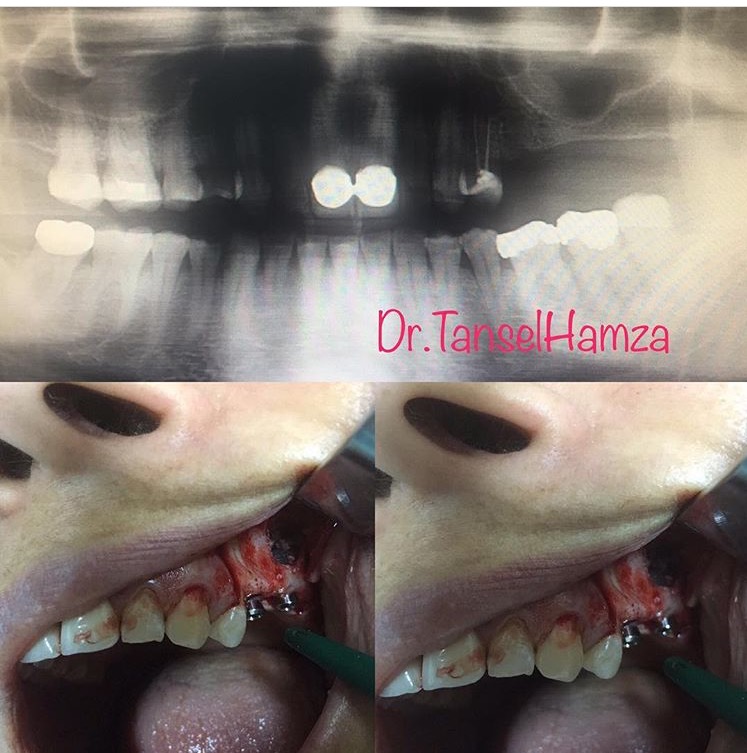

Tansel Hamza

Diş Estetiği ve İmplant (Bölüm 3)